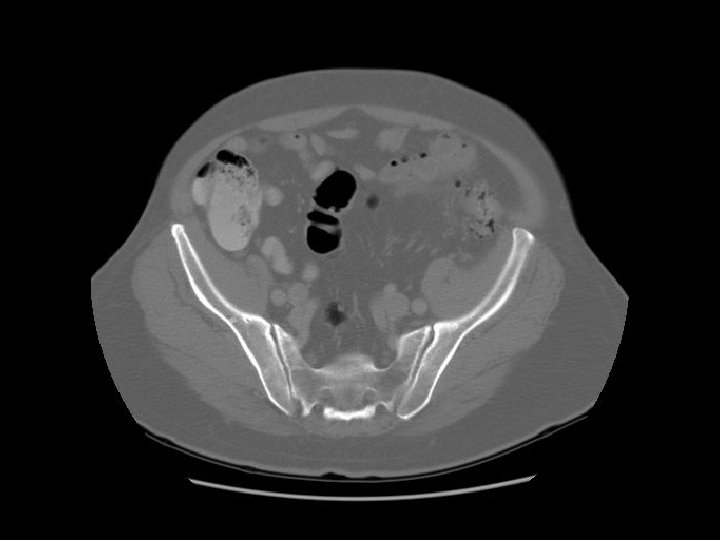

Arrows are pointing to the common iliac veins joining to form the IVC. Left

Ilium Sacrum

Arrows are pointing to the internal and external iliac veins joining to form the common iliac vein.